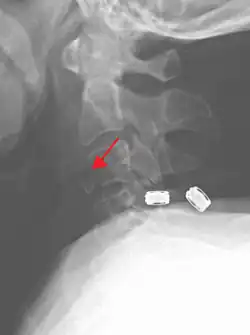

On CT scan or X-ray, a cervical fracture may be directly visualized. In addition, indirect signs of injury by the vertebral column are incongruities of the vertebral lines,[7] and/or increased thickness of the prevertebral space:[8]

![CT scan with upper limits of the thickness of the prevertebral space at different levels[8]](./_assets_/CT_of_prevertebral_space.jpg)